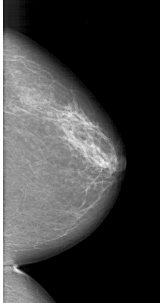

A_1415_1.RIGHT_CC

RIGHT_CC LINES 5746 PIXELS_PER_LINE 3031 BITS_PER_PIXEL 12 RESOLUTION 43.5 NON_OVERLAY